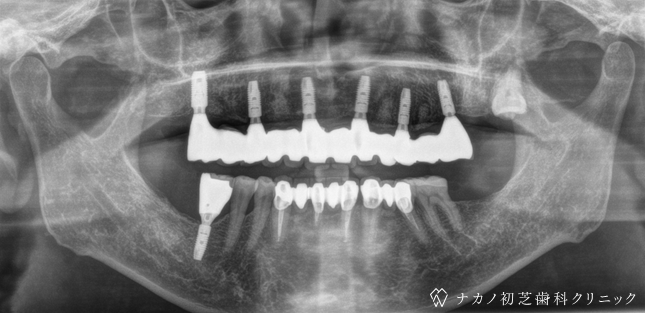

インプラント・7本 (60代男性)

-

BEFORE

AFTER

年齢 60代男性

治療内容 インプラント治療7本(骨造成の併用)

インプラント治療とは、歯を抜いた所にチタン製の人工歯根を埋入し、その上に歯を入れる方法です。骨を増やすことで、より審美的に治療が出来ました。費用 1本 400,000円(税込 440,000円)

リスク・副作用

腫れ・疼痛・違和感を感じるなどの症状を生じることがあります。